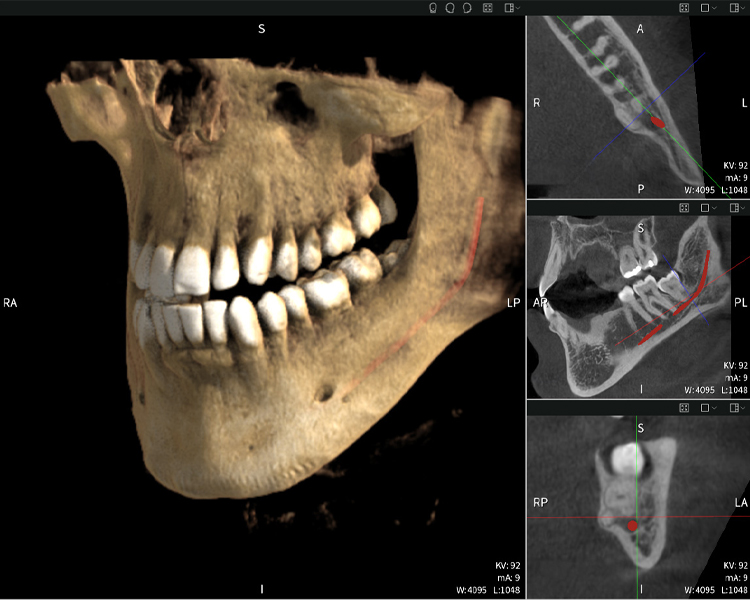

Figura b: Resultados de imagen de Seethrough Max, sobre un fondo negro.

Figura d: Resultados de imagen de Seethrough Max, sobre un fondo negro.

Las figuras b–d muestran varias vistas de una reconstrucción 3D de la mandíbula, proporcionando una visión general completa de la anatomía mandibular, la posición de los nervios en relación con los dientes y permitiendo evaluar la simetría y alineación dentaria.